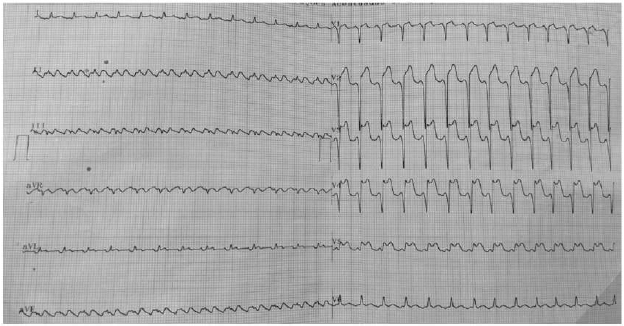

Paciente de 58 anos compareceu a um hospital regional do interior do Rio Grande do Norte. Durante o atendimento, relatou ter sentido dor precordial em aperto, associada à sudorese e mal-estar, com início há 5 horas, mas com piora há 20 minutos, após quadro de taquicardia. Foi medicado com AAS 300 mg e clopidogrel 300 mg, 5 mg de dinitrato de isossorbida sublingual, sem melhora da dor. Ao exame físico, apresentou: PA 110x60 mmHg, FC 156 bpm, auscultas cardíaca e pulmonar normais, boa perfusão periférica.

Realizou o eletrocardiograma reproduzido abaixo.